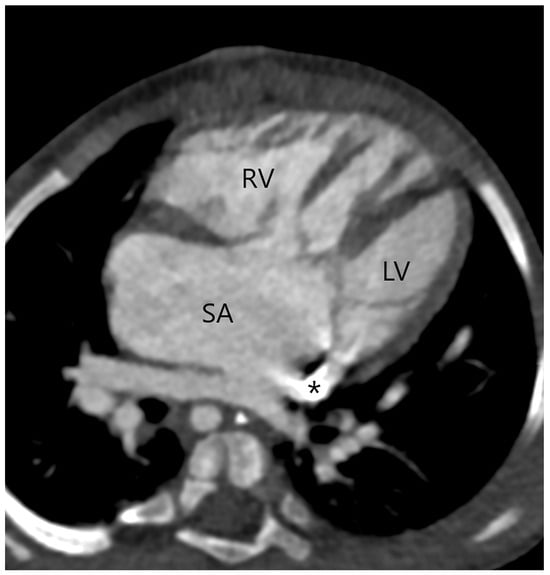

Figure 6.

Type B interrupted aortic arch in a patient with aortopulmonary septal defect type 2 (arrow); multiplanar reconstruction of CT angiography. The aorta (A) ends with bifurcation on the innominate artery (brachiocephalic trunk, I) and the left common carotid artery (C). Main pulmonary artery (MPA).